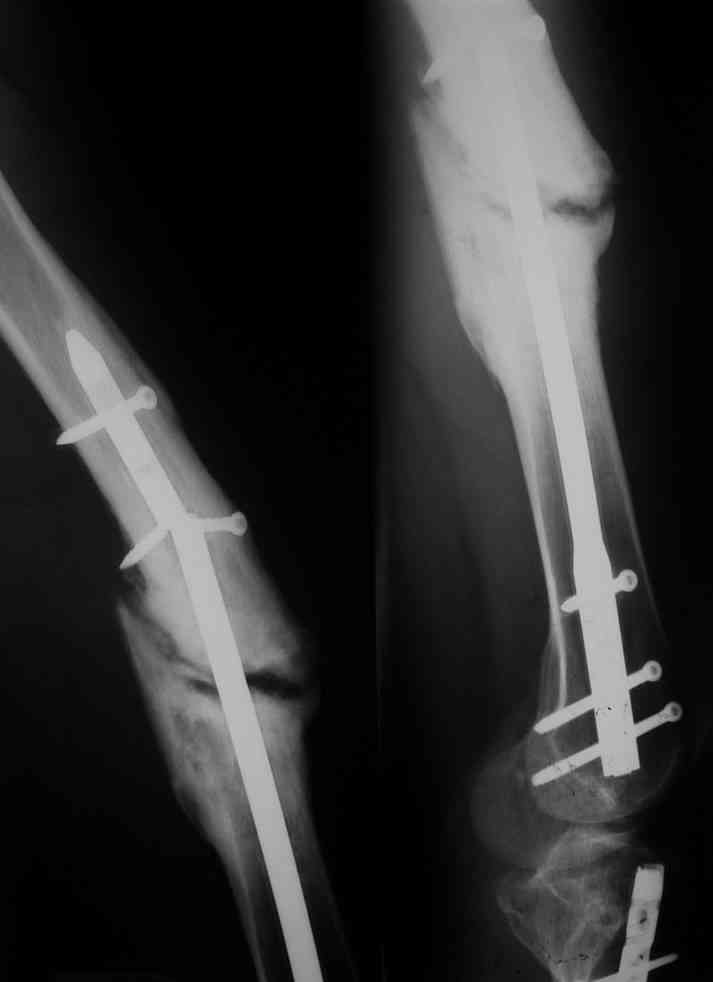

Re: Несостоятельность импланта

послал Бережной Сергей 10 Январь 2011, 19:07

Одной рентгенограммы недостаточно, чтобы планировать подобную операцию. Вот похожий случай, который пришлось оперировать 3 мес. назад. Тоже короткий гвоздь. Шляпки винтов проксимального фрагмента полностью погружены в костную ткань, чего уже достаточно для необходимости обнажения этой зоны. У этого же больного оказались полностью разрушены шлицы 2-х дистальных винтов, так что и там нужно было "открываться".